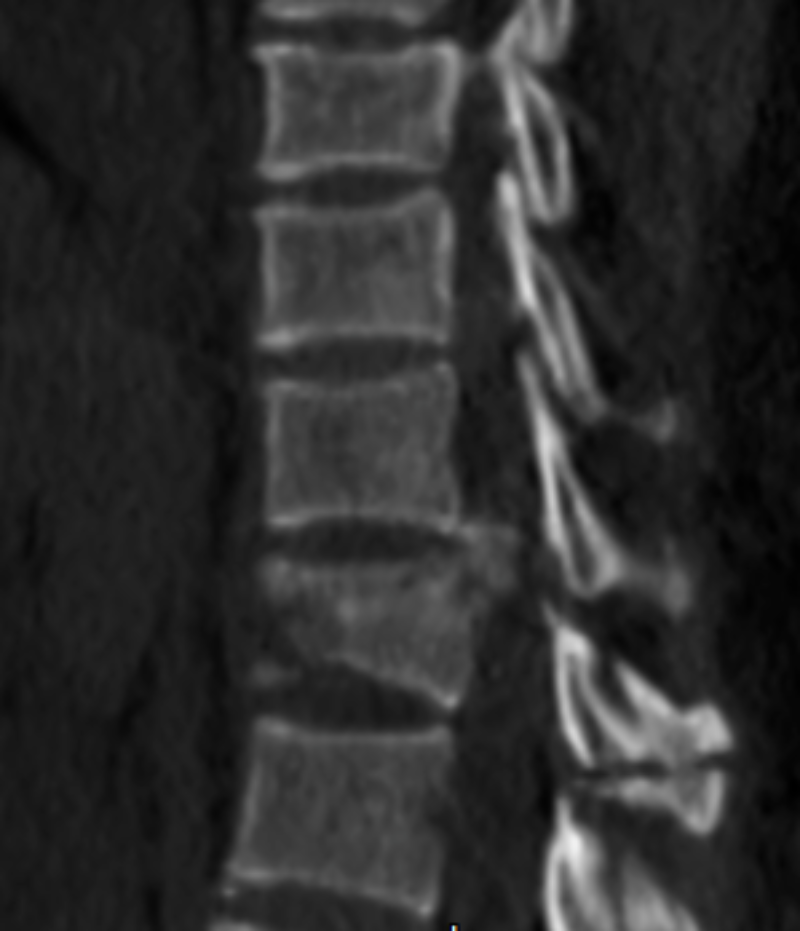

胸4椎體爆裂性骨折伴脫位